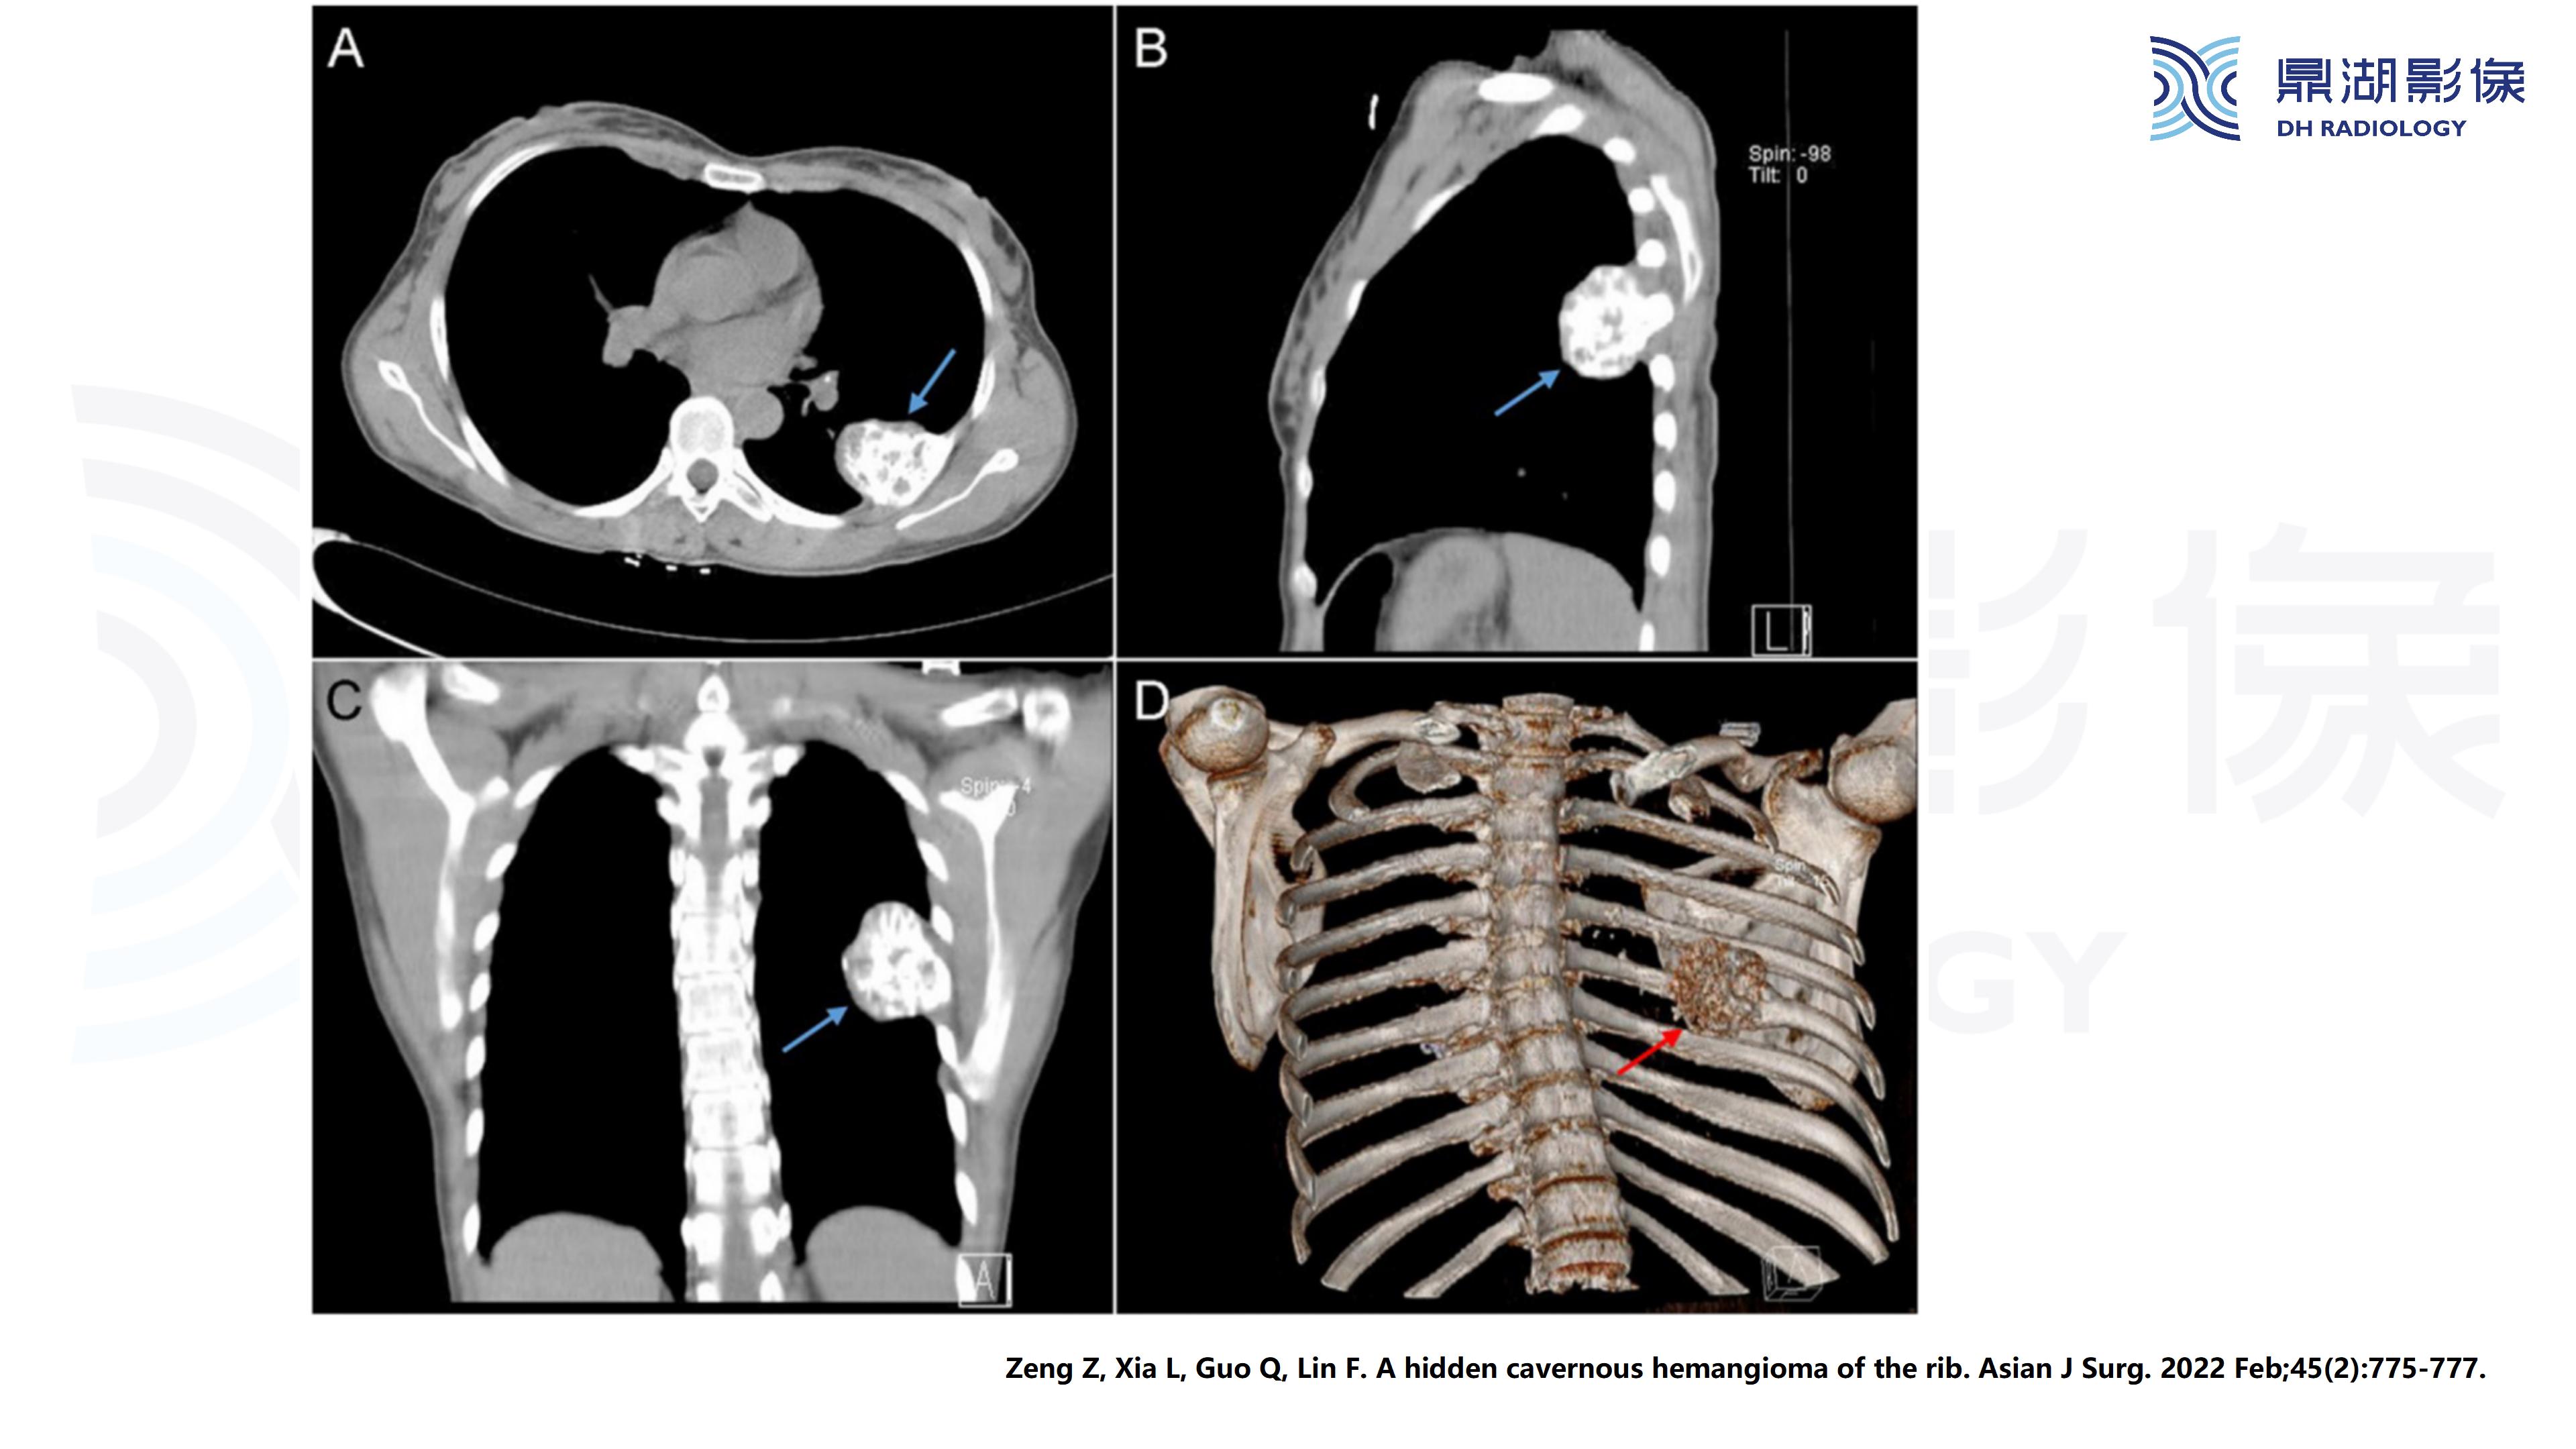

主诉:发现左侧胸壁局部隆起半年余

现病史:患者女,63岁,半年前活动后出现左侧胸痛,轻度胸闷,无咳嗽咳痰,无头痛头晕,无恶心呕吐,无腹痛等不适。温州大学第一附属医院就诊,未行治疗。半年来左侧胸壁隆起较前明显,活动后轻度胸痛症状,余无明显不适。